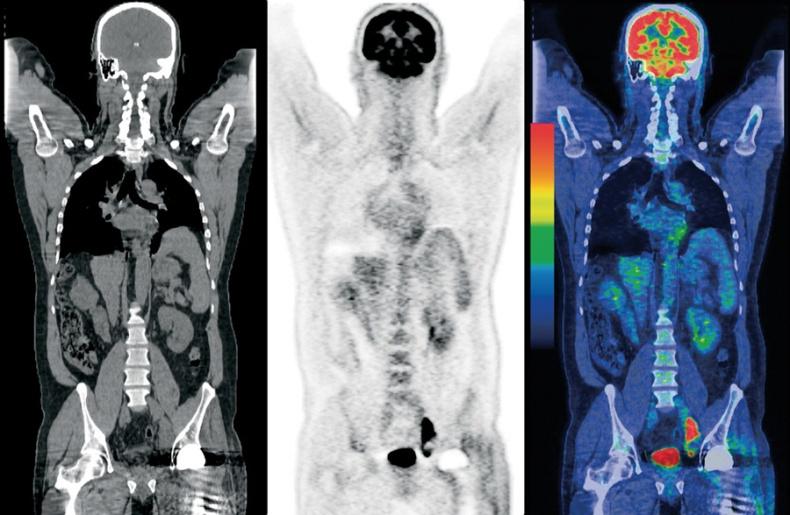

Сцинтиграфия, ОФЭКТ, ПЭТ

Пожалуй, это одни из самых редких процедур нашего списка. Эти методы обследований основаны на лучевой диагностике, только используется она наоборот. Пациента не облучают снаружи, а вводят ему специальный радиоактивный препарат, чтобы заставить “светиться изнутри”. Сначала учёными была придумана и опробована сцинтиграфия. С её помощью удавалось получить двухмерные изображения. Затем исследования пошли дальше и была изобретена однофотонная эмиссионная компьютерная томография (ОФЭКТ), а вслед за ней и позитронно-эмиссионная томография (ПЭТ). Разница между этими методами скорее техническая, в них используются разные радиофармпрепараты и разные типы детекторов, которые фиксируют излучение из тела пациента.

Возникает вопрос: “Зачем такие сложности?”. Дело в том, что благодаря этим процедурам на снимках можно увидеть образования, которые не видны на снимках, полученных путём внешнего облучения. Метастазы и опухоли могут появляться внутри костей или органов и долгое время не проявляться. Радиофармпрепарат вводится внутрь организма и накапливается в тканях, что позволяет “подсветить” определённые участки.

Основной минус этого метода обследования — стоимость. Радиофармпрепарат разрабатывается индивидуально для каждого пациента, кроме того, пациент получает лучевую нагрузку, да и сама процедура более сложная, нежели те, которые мы описывали ранее. Однако в некоторых случаях без неё не обойтись, например, при онкологических и неврологических заболеваниях, диагностике болезней сердца и щитовидной железы.

Гибридные методы визуализации

Наверное, наука не была бы наукой, если бы постоянно не двигалась вперёд и не пыталась создавать новое из старого. Так, врачи начали объединять различные методы сканирования, чтобы получить ещё более подробное и качественное изображение. ПЭТ и ОФЭКТ объединяют с КТ, МРТ дополняют ПЭТ. Такие эксперименты стоят недёшево, но иногда могут помочь принять решение о дальнейшем лечении пациента.